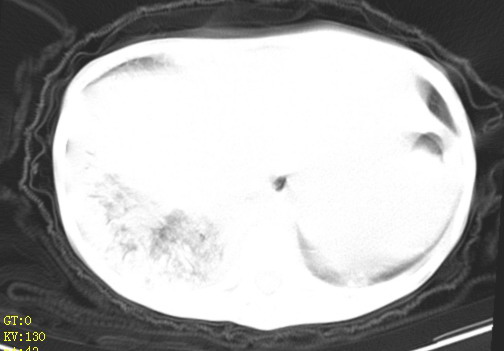

女,12岁,气促、咳嗽2天,3个月前查胸片示:两肺感染,急诊入院查ct,血常规等未检查。

1、左心房、左心室增大,考虑左心衰, 2、肺水肿合并感染 3、双侧胸腔积液

双肺中下野不规则片絮状阴影,中外带明显,双侧胸腔少量积液,心影增大,心腔密度减低,隆突下及左侧气管旁见钙化淋巴结影,考虑双肺感染、心衰;建议结合临床除外h1n1并急性心衰,先心不能排除。

两肺多发片絮状模糊影,以下肺外带居多,内见支气管气像,纵膈窗未减影,两侧胸腔积液,心影增大,结合心超,支持重症肺炎,非常时期,甲型h1n1流感不排除。